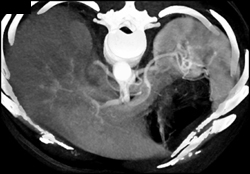

Dissection Involves the SMA